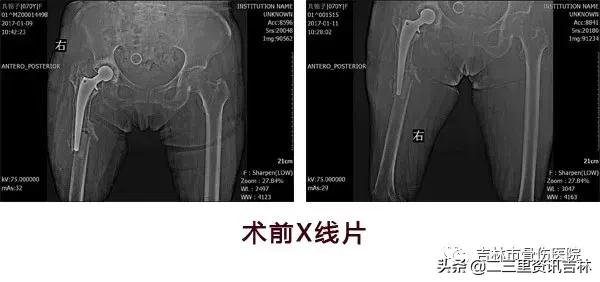

患者,女,70岁。

该患于2008年6月因“右股骨颈骨折”在外院行“右侧髋关节置换术”,术后恢复良好,休养至今,于2016年11月30日在自家走路时不慎滑倒摔伤,伤后出现右髋部肿痛,不敢活动,未经处置,在家休养至今未见缓解,现为求系统治疗前来我院就诊,经门诊医生查体拍片后以:“右侧髋关节置换术后假体周围骨折”收入院。

患者入院后给予常规检查,经三级医师查房,临床诊断确诊,查无明显手术禁忌症后在腰硬+全麻麻醉下行“右侧髋关节置换术后假体周围骨折关节翻修术”,术后抗感染、消肿、抗凝、关节功能松动练习等对症治疗,术后患者恢复良好。